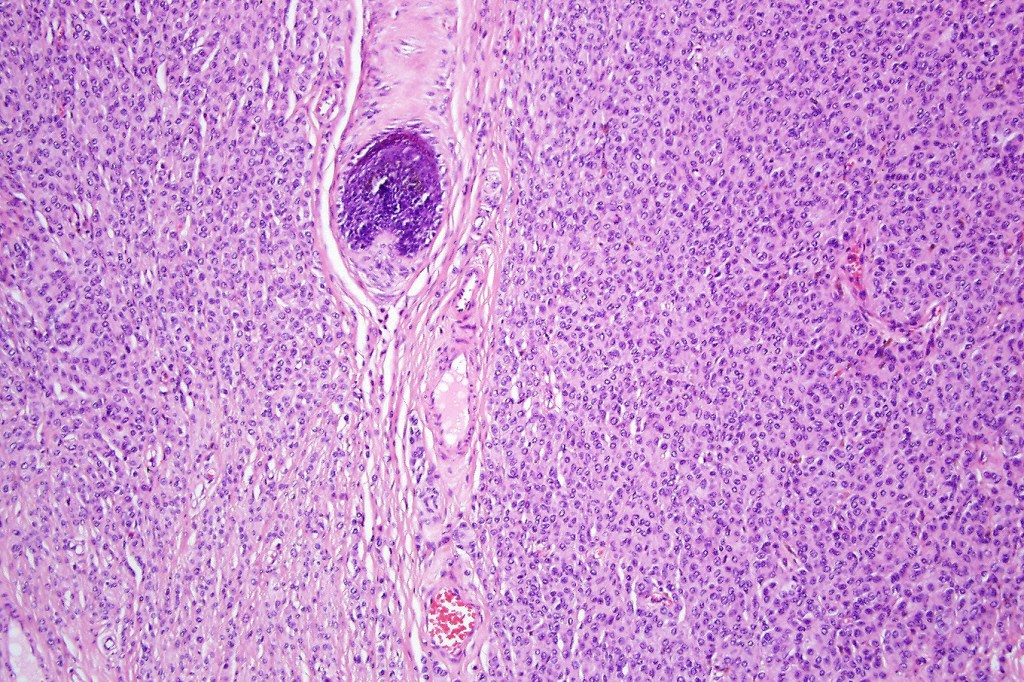

•The nodule generally merges with the adjacent nevus but sometimes it can be sharply circumscribed

•It is hypercellular and most often composed of epithelioid cells showing little pleomorphism & only occasional mitoses

•Some examples show more marked pleomorphism with prominent nucleoli and increased mitotic activity but abnormal mitoses are not a feature. These are not associated with any sinister biological potential

•Absence of necrosis, hemorrhage or Pagetoid spread in the overlying epidermis

•Spindle cell, small blue cell, blue nevus-like features, Spitzoid & proliferative nodules with mesenchymal differentiation (myofibroblastic, chondroid & osteoid) can be seen